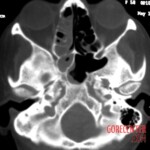

Further examinations, including blood tests, did not reveal diabetes or other common conditions that could explain the symptoms. However, it was evident that the body was fighting a severe infection. A crucial turning point came with a CT scan, which revealed extensive damage to the maxillary bone and spread of inflammation into the paranasal sinuses, including the deeper ones. Fortunately, the brain and eye sockets were not yet affected.